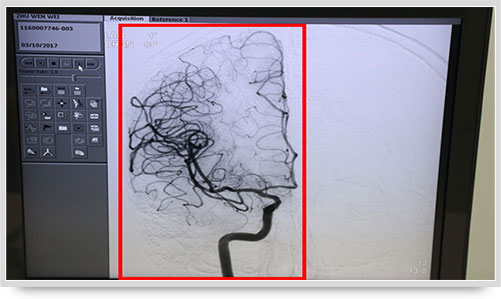

同時,手術(shù)臺前的液晶顯示儀屏幕上清晰地現(xiàn)顯出導(dǎo)管的路徑,在李主任的操作下準(zhǔn)確到達(dá)指定檢查部位,各條血管的“廬山真面目”清晰可見。

45歲的朱姓患者因“多發(fā)性腔性腦梗塞”頭暈不明,接受了全腦血管造影術(shù),術(shù)中顯示他的顱內(nèi)椎動脈血管痙攣(紅圈內(nèi)為病變部位)。據(jù)李主任介紹,以前像腦梗塞等腦血管疾病只能被定位到腦的功能區(qū)域,無法確定責(zé)任血管,而實施全腦血管造影術(shù)就能精準(zhǔn)地找出病變血管,好比揪出了造成腦梗塞的“禍?zhǔn)?rdquo;,大大提高了腦血管疾病的診治水平。

之前,另一位61歲的李姓腦出血患者,康復(fù)治療半個月后復(fù)查,也接受了全腦血管造影術(shù),術(shù)中顯示大腦前動脈A1段動脈瘤(不同維度顯影,紅圈內(nèi)為動脈瘤瘤體)。像這樣的病人,必須進(jìn)一步進(jìn)行手術(shù)治療,及早清除動脈瘤,避免因瘤體破裂造成再次出血危及生命。